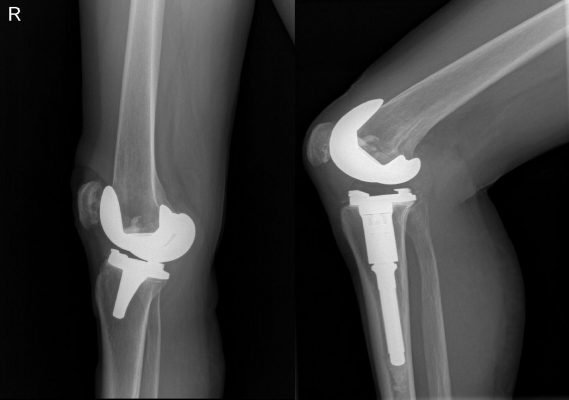

En qué Casos Utilizar Prótesis en Rodilla: Cuando existen daños severos en las rodillas, se tiende a hacer una cirugía en la que se inserta una prótesis total de rodilla. Esta nueva rodilla es de materiales espaciales que aliviarán el dolor y harán que se mantenga la función de la misma para el paciente.

Las prótesis de rodilla tienen una duración de entre 25 y 35 años; pero no durará más de ese lapso, puesto que como todo material, va a irse desgastando y aflojando. Por esta razón, una vez que pase dicho tiempo, comenzarán a sentirse los síntomas de aflojamiento. A los pacientes jóvenes no se los ponen porque en algún momento de su vida tendrán que hacer un cambio de prótesis.

En el caso de los pacientes jóvenes debe hacerse el intento de mejorar la situación a través de otras intervenciones quirúrgicas menos invasivas como la artroscopia o la osteotomía, que permitan que el miembro a alienar lo consiga (En qué Casos Utilizar Prótesis en Rodilla, Cirugía de Rodilla).